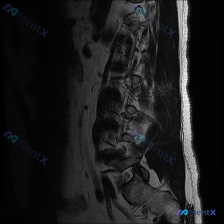

看到这份腰椎MRI的片子,整理了完整的读片和分析思路跟大家分享一下。 病例基本影像信息 这是一份腰椎矢状位T1加权MRI图像,图像质量清晰,没有明显运动伪影,显示了L1-L5全腰椎节段,还有部分胸腰结合部和骶骨: 1. 腰椎生理前凸存在,椎体排列规整,没有明显滑脱或侧弯 2. 各腰椎椎体形态正常,没...

今天整理了一份有意思的胸椎MRI读片病例,跟大家分享一下,核心问题是初始找椎间盘病变,结果发现了更关键的病变,先把影像资料和分析思路整理给大家。 一、影像基础信息 这份是胸椎MRI矢状位T2加权图像,覆盖T1到T12全胸椎序列,图像质量尚可,无明显伪影,胸椎生理后凸曲度存在。 二、常规评估结果 1....